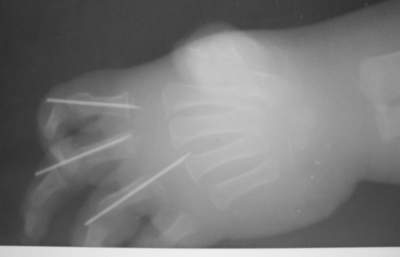

Dear collegues,В прошлое воскресенье (по дежурству) привезли одного ребеночка из соседнего городка.Травма - ребенок засунул руку в электромясорубку за 2 суток до попадания к нам (в пятницу).По месту жительства - ПХО, спицы....

До сих по не могу смотреть без содрогания.Мальчику - 2 годика, правая ручка.Кистевики говорили, что 2,3 и 4 пальцы придется отрезать, попробуют разве что только побороться за основные фаланги (завтра узнаю подробнее ибо уже прошла неделя).P.S. Судя по поведению матери в приемном покое мясо крутила именно она... а отец был так НЕХОРОШО и ЗАДУМЧИВО УГРЮМ...-- Best regards,~~~~~~~~~~~~~~~~~~~~~~~~~~~~~~~~~~~~~~~~~~~~~~Aleksey V. Mozgounov

Вроде бы на представленных фото пальцы жизнеспособны... ( снимки сразу после обработки или на момент госпитализации к вам, 2 дня спустя ?)

На 3-4 сутки обычно становится очевидно - что выживет, а что уйдет при повторно обработке.

Если перфузия пальцев сохранится, то прогноз должен быть благоприятным - у детей удивительные репаративные способности. При первичной обработке таких повреждений интаоперационно невозможно определить демаркацию травмы мягких тканей, поэтому обработка по сути сводится к тщательному промыванию ран и адаптации кожных лоскутов редкими швами, после 3-4 дней, когда зона демаркации становится различимой - повторная обработка.